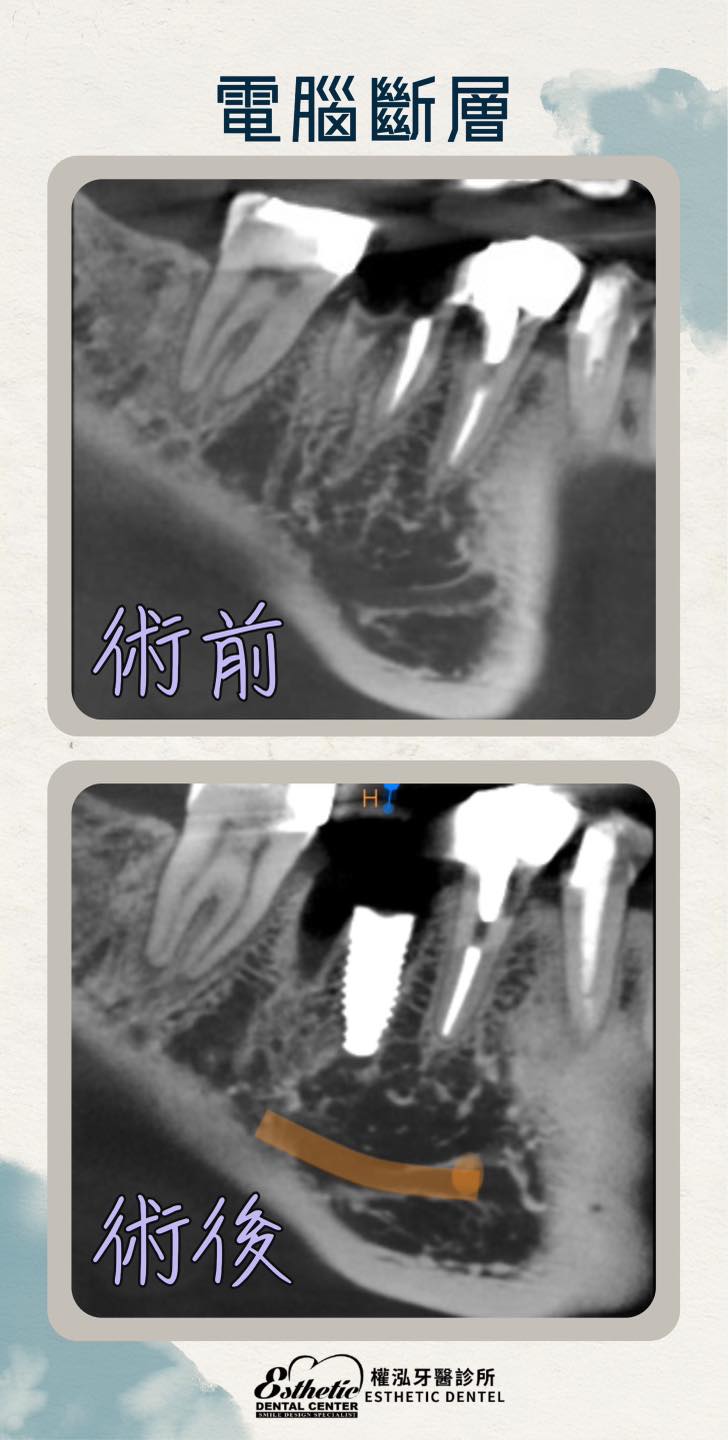

什麼是手術導板? 手術導板是一種精準設計的數位工具,在植牙前,我們透過3D掃描與電腦斷層模擬,規劃出最理想的植體位置與角度,再利用導板引導植牙過程,讓手術更快、更準、更安全!

真實案例分享-今天我們治療了一位患者,H小姐意外把牙齒咬斷了…影響咀嚼功能。原本擔心要經歷拔牙、等待癒合、再植牙的漫長過程,沒想到透過數位手術導板的輔助,我們得以精準定位植體角度與深度,讓拔牙、補骨以及植牙手術更順利、更安全。

有沒有想過,當牙齒因意外斷裂或嚴重受損時,是否只能先拔掉再慢慢等待植牙呢?其實,如果條件狀況允許的話,可以透過手術導板輔助的即拔即種技術,我們可以在同一次療程內完成拔牙與植牙,我們讓這位患者當天拔牙、當天植入人工牙根,術後竟然 完全不痛,順利恢復!不僅大幅縮短療程時間,還能減少手術對口腔組織的影響,讓患者更快恢復正常生活!